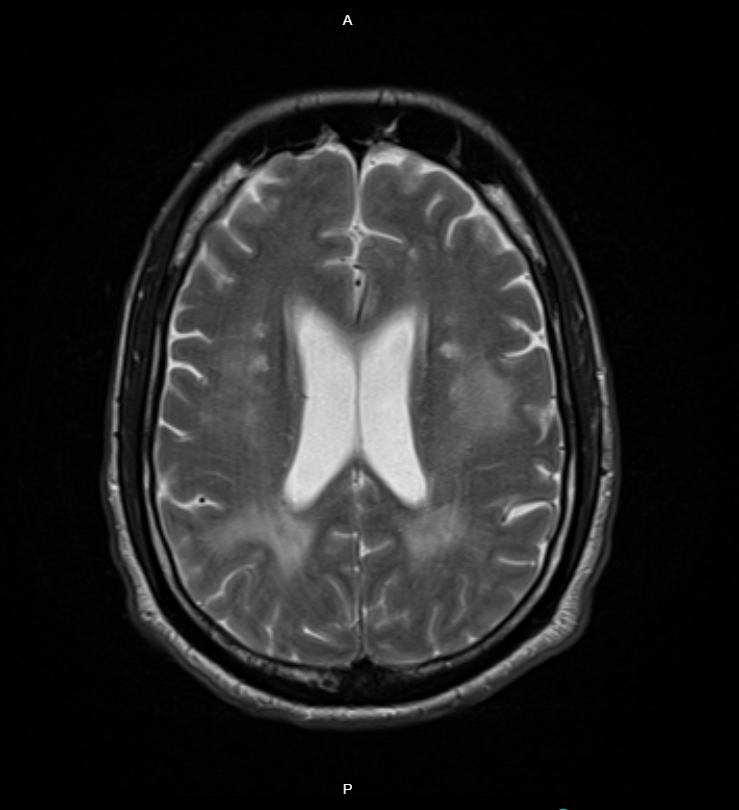

A Head CT showed diffuse white matter hypoattenuation concerning for vasogenic edema or posterior reversible encephalopathy syndrome (PRES). He received 25 mg IV hydralazine and started an IV nicardipine drip, lowering his SBP to 200 mmHg within the first hour and admitted to MICU.

After 48 hours, head MRI showed new punctate infarcts consistent with lacunar strokes. MRI Angiography was unremarkable. The patient developed altered mental status, hypotension, and respiratory failure requiring intubation. Repeat CT head showed new right frontal hypoattenuation suggestive of infarction. Antihypertensives were held, and bumetanide drip started for suspected pulmonary edema. After 48 hours, continuous renal replacement therapy was initiated due to worsening renal function. He was extubated on day 5. On day 9, he developed expressive aphasia with preserved strength. He was stabilized and discharged with multidisciplinary follow-up.